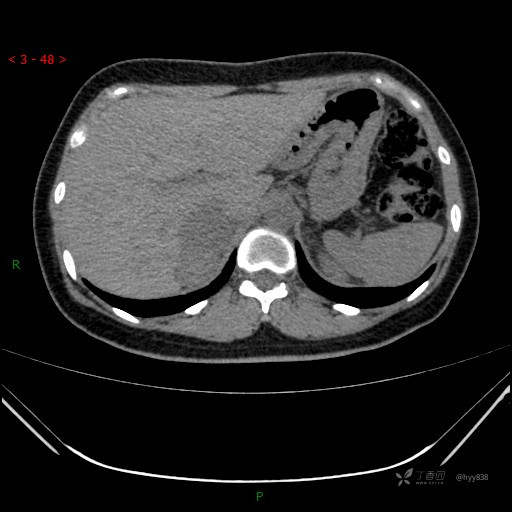

辅助检查:CT

肾上腺CT平扫